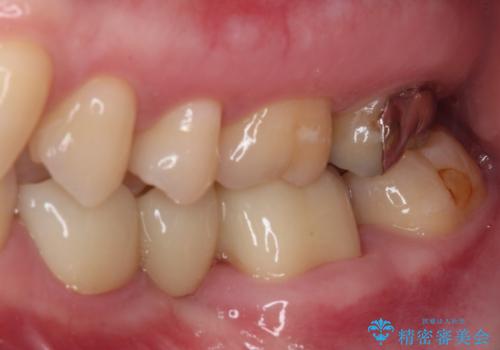

- 近医で奥歯が割れているので抜歯が必要と言われたとのことで来院された患者様です。

診断の結果、歯根が縦に破折しており抜歯が必要な状態でした。

継ぎ接ぎだらけの上顎前歯もオールセラミッククラウンにて審美的に改善したいとのことでしたが、捻れが強くあるため、事前に矯正治療で歯列を整えてから、補綴治療を行うこととしました。